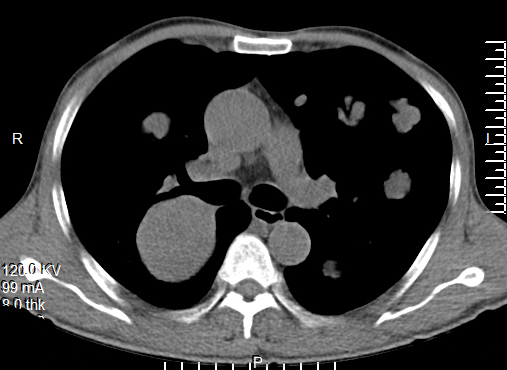

[影像描述]

双肺多发转移灶,大小不等,呈棉花团样

CT表现为粟粒、单发、多发大小不等结节,呈圆形或椭圆形,密度均匀、轮廓清楚,肺野为著。

1、肺内单发或多发球型结节影,大小不一,边缘光滑,密度均匀,多分布于肺外围

2、肺内软组织团块影!单发或多发,有分叶或毛刺,部分有空洞

3、两肺布满粟粒样结节

4、肺纹理呈网状改变或沿淋巴管呈细小结节状改变,HRCT表现为小叶间隔增厚,沿肺纹理有细小结节影,同一患者出现多种形态转移征象.